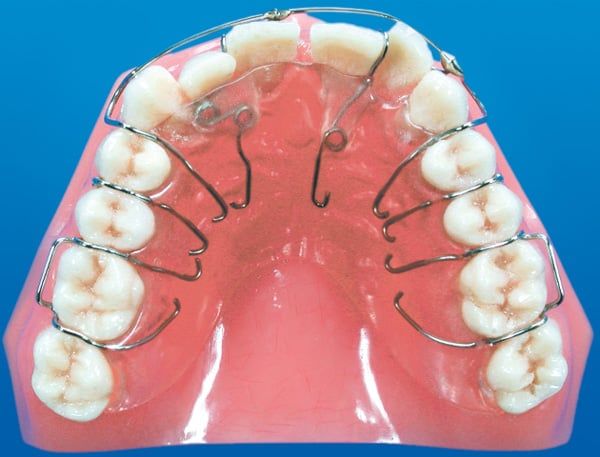

Multi-Spring Appliance

Minor tooth movement may be necessary to position teeth properly as permanent teeth erupt during the growth process. In adults, minor tooth movement procedures in conjunction with restorative care can be used in many ways to enhance a patient's appearance.

This removable appliance is used to accomplish multiple tooth movements. The objective is to close the space between the front teeth, create room in the arch for the blocked out lateral teeth and guide them into place. To accomplish the numerous movements, springs are used to move the teeth and close the spaces.